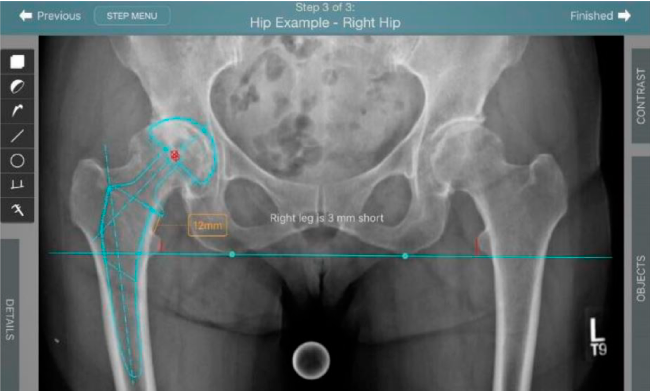

Planeación preoperatoria mediante la creación de plantillas digitales para reemplazo de cadera y análisis intraoperatorio

• Aumenta la precisión y reproducibilidad quirúrgica generando resultados predecibles.

• Datos procesables en tiempo real para la toma de decisiones.

• Mejora los resultados de los pacientes disminuyendo riesgos.

• Favorece la restauración biomecánica del offset femoral.

Beneficios de la planeación preoperatoria con Velys Hip Navigation ™

• Disponibilidad de plantillas digitales de cadera.

• Expediente histórico y personalizado, optimiza la planeación con el calendario de casos realizados en Velys TM y utiliza los íconos interactivos para una rápida revisión.

• Espacio colaborativo: puede compartir los casos entre cirujanos y sus equipos mediante la funcionalidad de intercambio de información.

• Anotaciones digitales y herramientas de análisis de longitud de pierna.